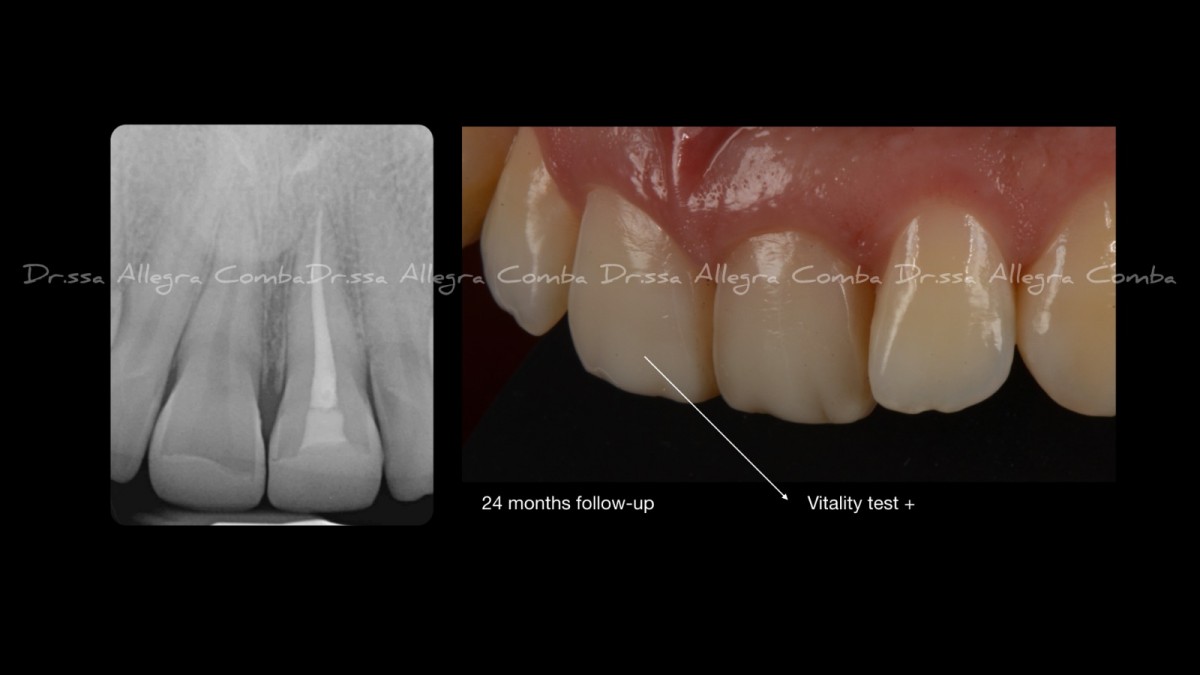

Adhesive procedures were carried out with a two-step self-etch adhesive system with selective enamel etching for 30s. An indirect pulp capping was performed on 3.6 with an MTA-based photo-curable material (Fig.6).

3.4 and 3.5 cavity cleaned. The mesial area of 3.5 was found to be only demineralized, and therefore not requiring restorative treatment. The horizontal slot approach on 3.4 failed, due to insufficient dentinal sustain to the cuspal crest, leading to a conventional vertical approach (Fig.8).

Detail of 3.5 mesial area, showing the demineralization without cavitation. In order to avoid further damage and to protect the demineralized enamel, a resin infiltration with a dedicated system was performed (Fig.9).